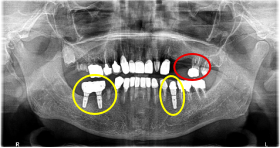

Before

※赤丸を抜歯しました。

After

※赤丸は、歯根が破折していたため抜歯しました

※黄色丸は、2006年10月に埋入したインプラント